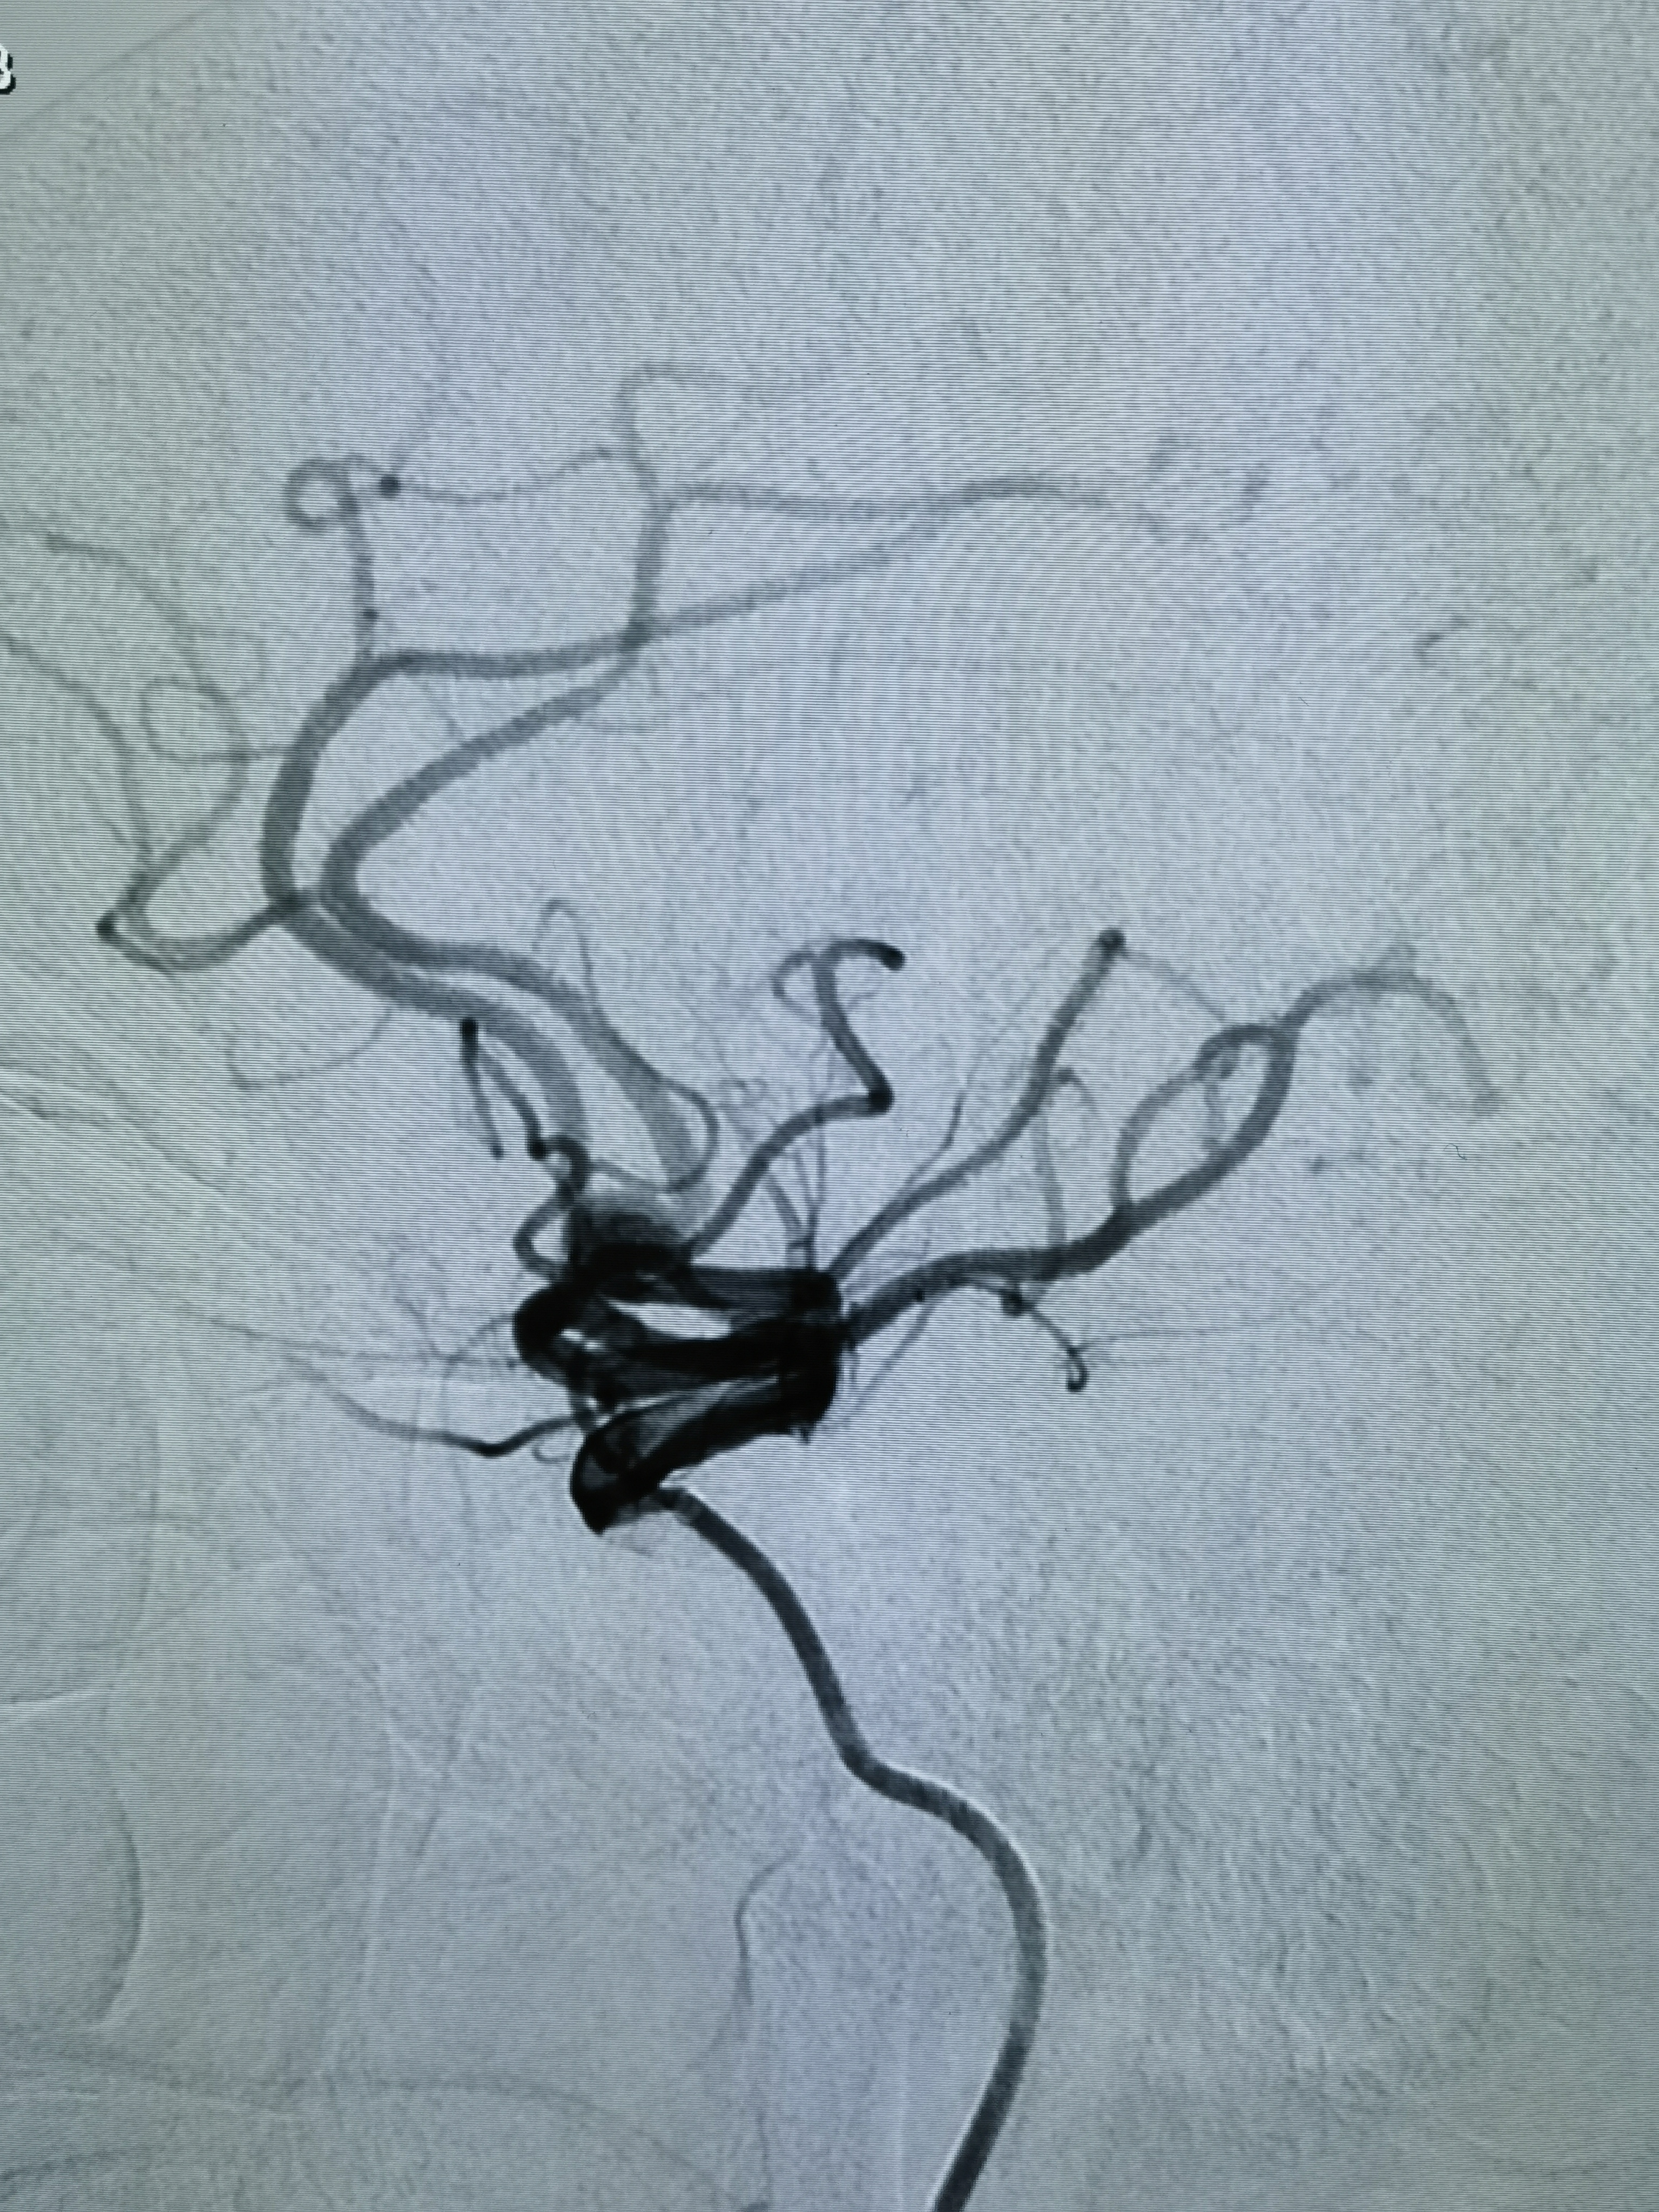

女性,63岁,体检发现动脉瘤,造影显示动脉瘤带子囊,破裂风险大,手术干预!

侧位造影